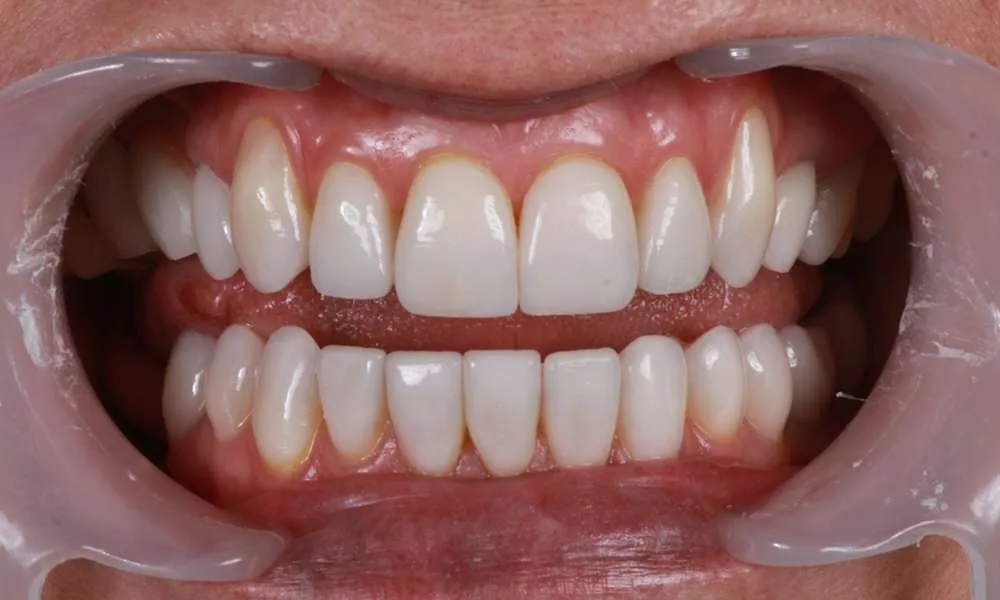

Real Stories, Real Results: Case Studies Showcasing How Our Personalized Approach Transforms Smiles and Lives

Complex Cases

Witness the Remarkable Changes We Can Achieve